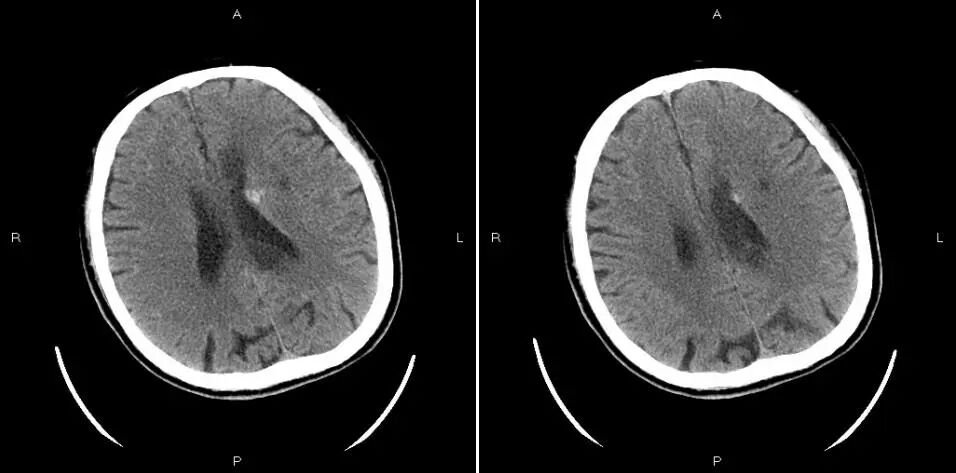

术后第七天复查颅脑CT渗血面积减小密度明显减低,继续双抗治疗。查体:右侧肢体肌力4级,右侧巴氏征阳性,NIHSS评分4分,出院。